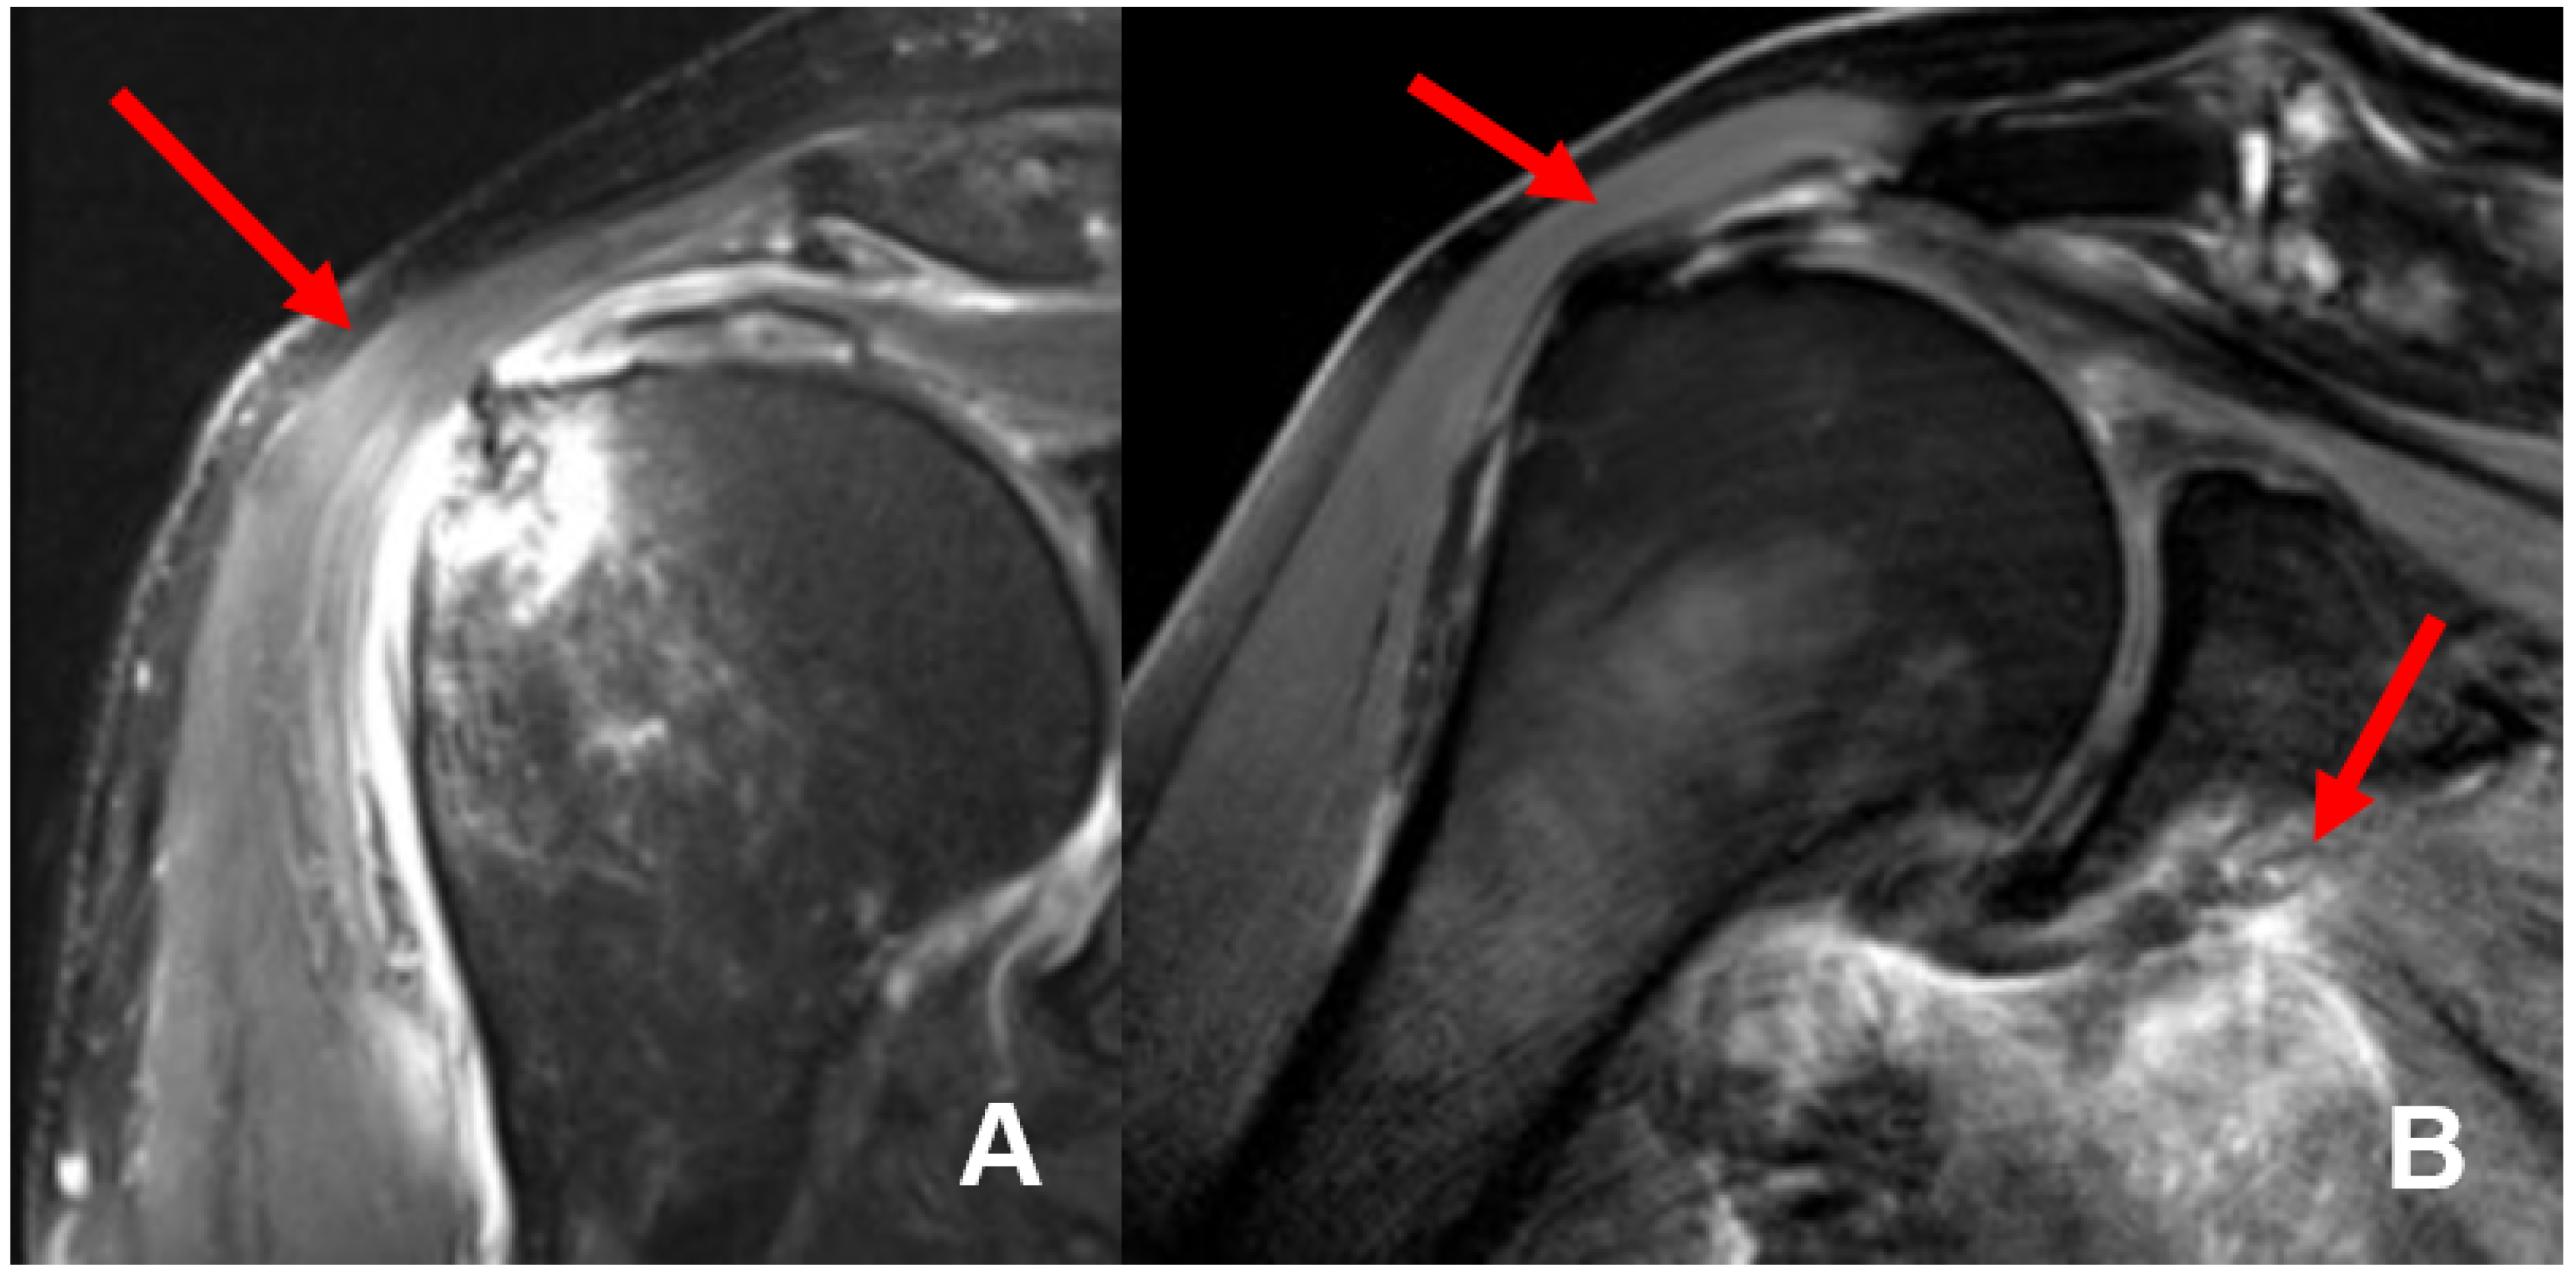

The mean interval between trauma and MR imaging was 6.9 days (0–14 days). In 8 of 21 patients (38%), we found 11 concomitant intra-articular glenohumeral lesions. In three patients (14.3%), two lesions occurred at the same time. In total, three partial bursa sided tears of the supraspinatus tendon (14.3%) and five (23.8%) partial articular sided supraspinatus tendon tears were found. Two patients (9.5%) had a partial tear of the subscapularis tendon Fox and Romeo I (9.5%), whereas only one (4.8%) complete transmural supraspinatus tendon tear was detected (see Figure 4). In none of the detected concomitant intra-articular glenohumeral injuries, a fatty degeneration or/and atrophy of the rotator cuff musculature was found. Moreover, indirect signs of acute rotator cuff injury were found in terms of the 1st bone bruise of the lesser and respectively the greater tuberosity and 2nd joint effusion in terms of acute hematoma; so that the injuries were considered as an acute traumatic tear (see Figure 5).

Figure 5. MRI imaging of a complete transmural tear of the supraspinatus tendon (A) and complete supraspinatus tendon tear at the foot print with intramuscular hematoma of the musculus subscapularis (B) detected in our study.